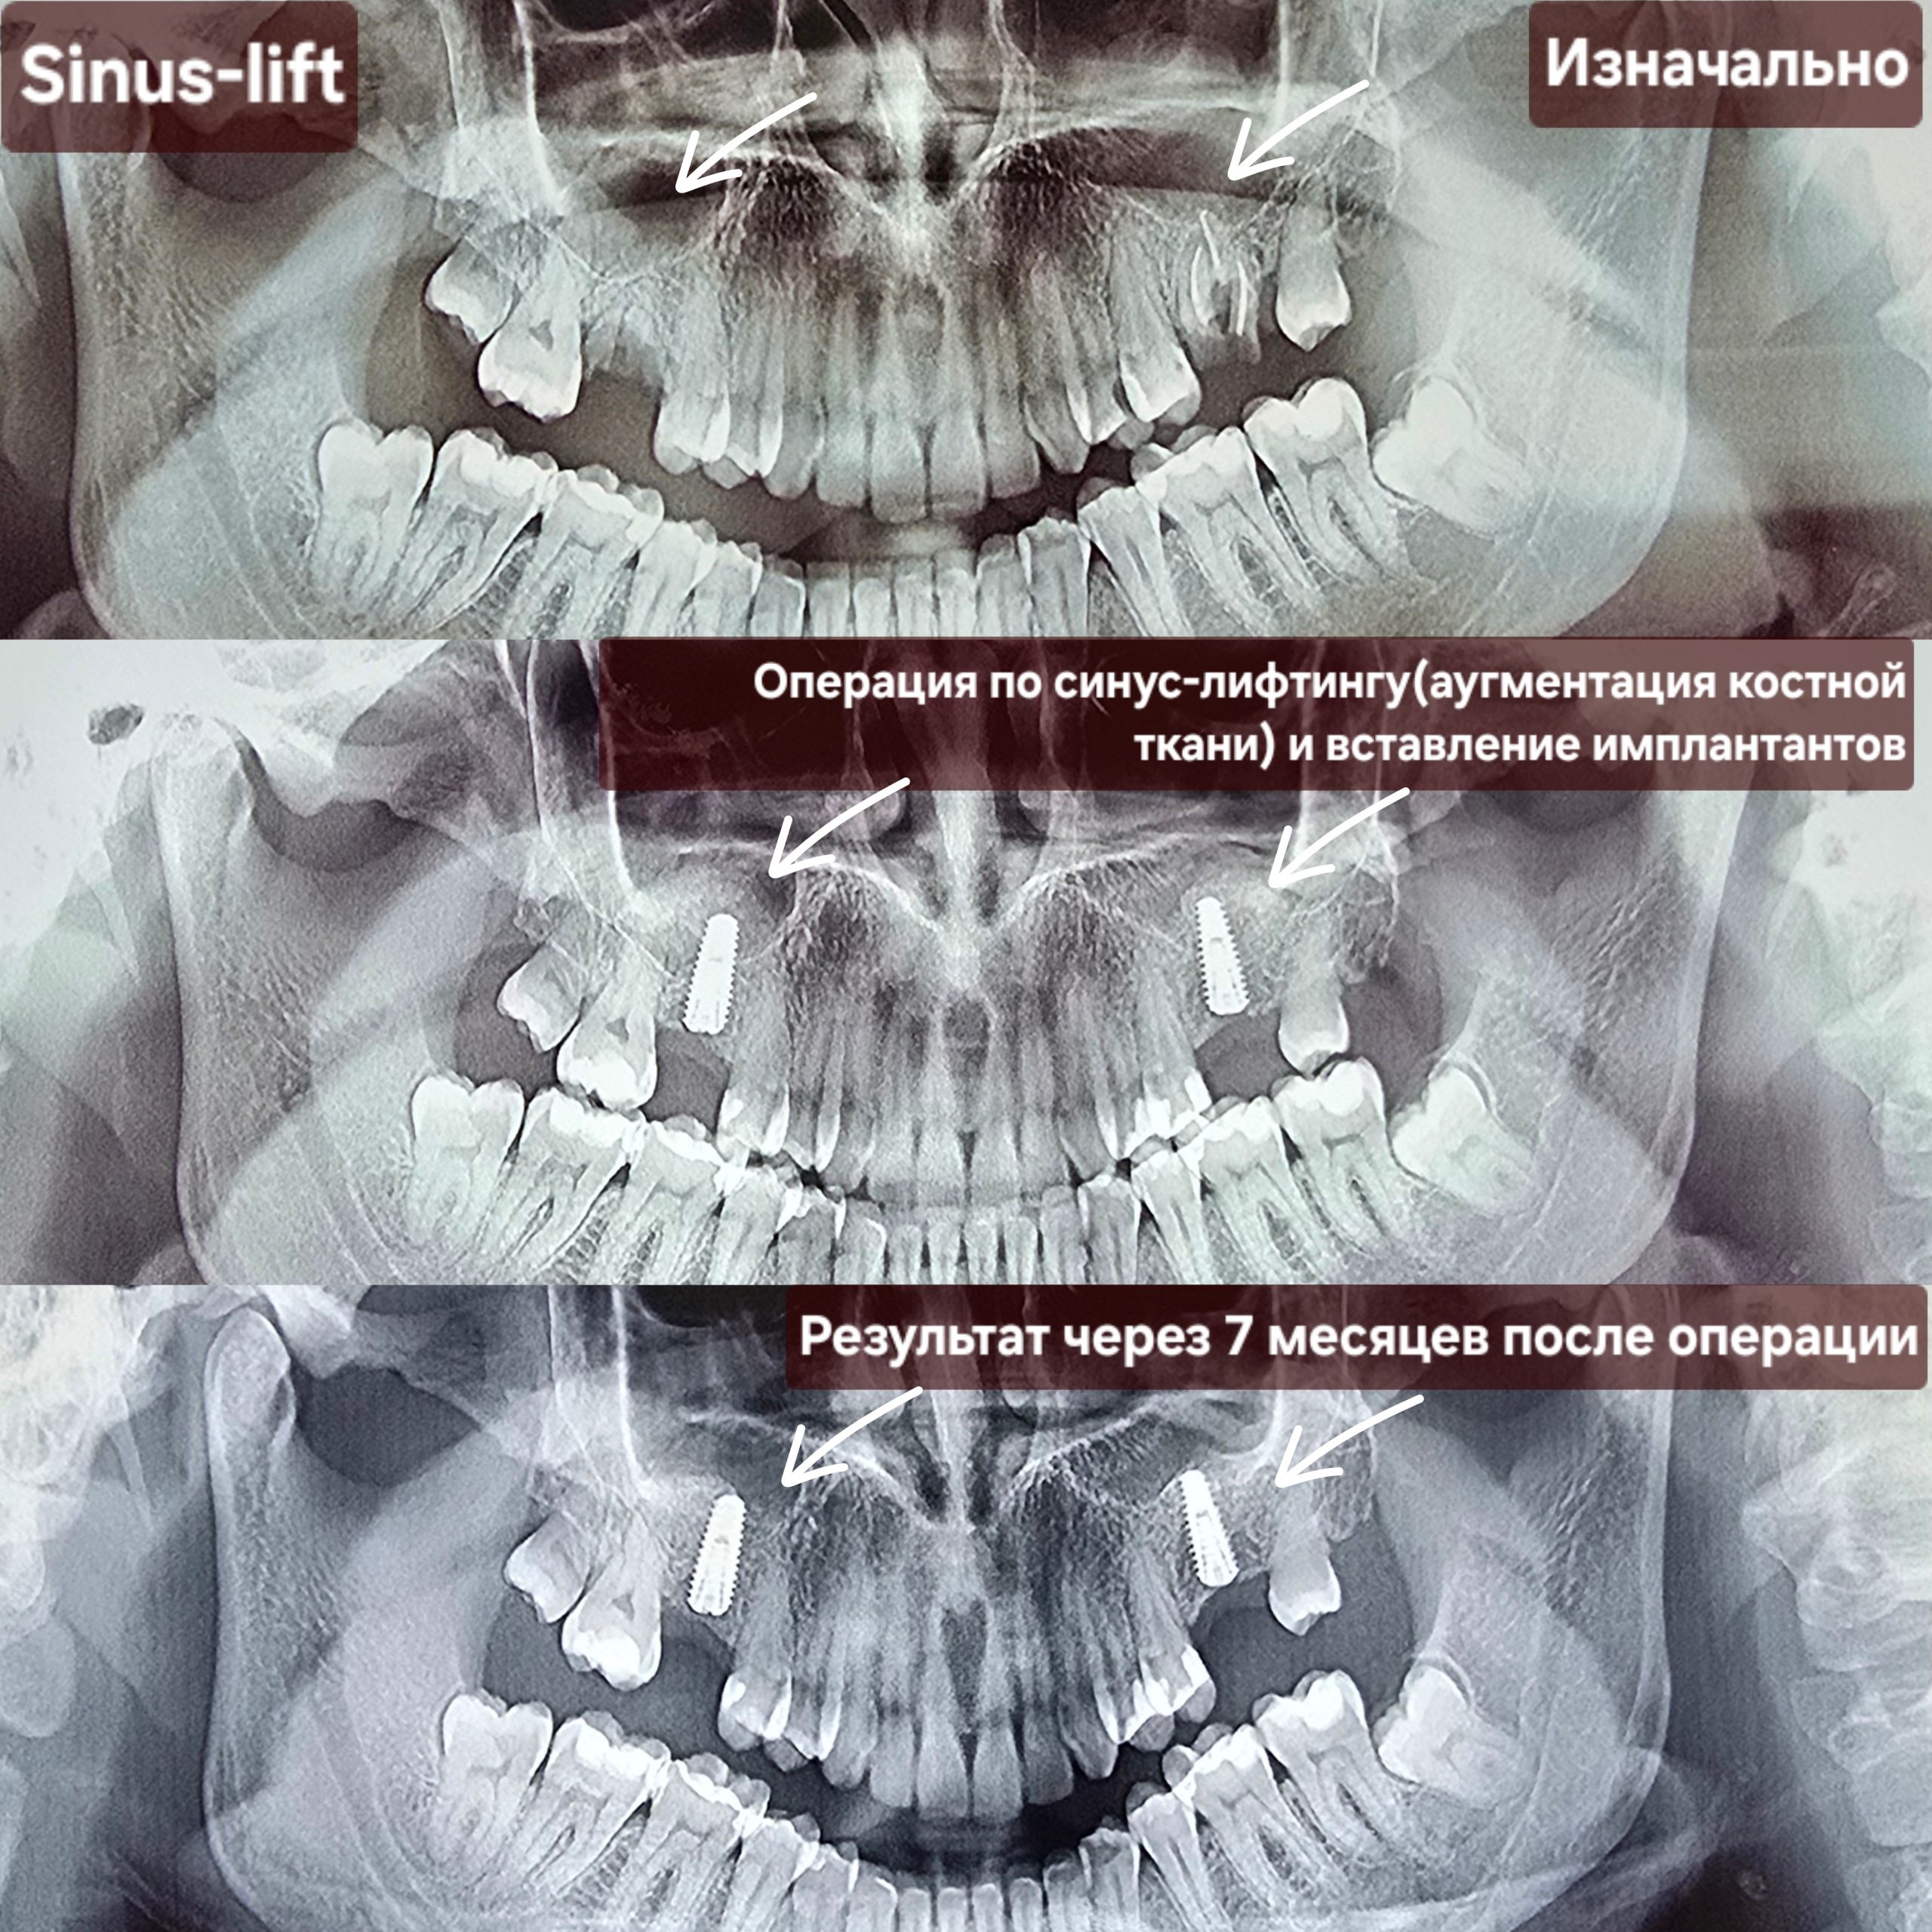

Cea mai răspândită intervenție de augmentare osoasă în stomatologie este operația de sinus lift (ridicarea sinusului) – o procedură chirurgicală de adiție osoasă realizată la maxilarul superior pentru a crește volumul osos necesar inserării implanturilor dentare. Prin ridicarea membranei sinusale și introducerea unui material de grefare, se creează o bază solidă, fiind necesară când sinusurile sunt prea coborâte sau osul este prea subțire. Scopul acestei proceduri este crearea unui suport stabil pentru implanturi dentare în zona laterală superioară (molari/premolari). Procedura de adiție osoasă se efectuează sub anestezie locală. Vindecarea durează de obicei între 4 și 6 luni.

Implantarea și ridicarea sinusurilor permit restabilirea zâmbetului estetic chiar și în cazurile extrem de dificile, adică și în situațiile când pacientul se adresează tardiv. Înainte de apariția acestei tehnici, unii pacienți trebuiau să se mulțumească doar cu proteze și punți mobilizabile. Odată apărută posibilitatea creșterii osoase, contraindicațiile pentru instalarea implantelor au fost considerabil reduse.